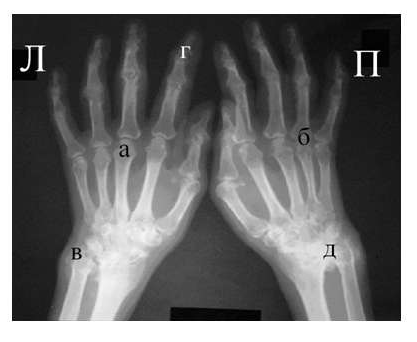

Рис. 4. Изменения кистей при ревматоидном артрите (а остеопороз, бсужение суставных щелей, в кистовидные просветвления, г костные эрозии, д анкилозирование)

Необходимо также помнить, что, как правило, при РА эрозии не предшествуют околосуставному остеопорозу, кистам и сужению суставных щелей. Имеет место последовательность развития стадий РА (см. рис. 4), в отличие от эрозивных артритов другого генеза (псориатического, серонегативного)